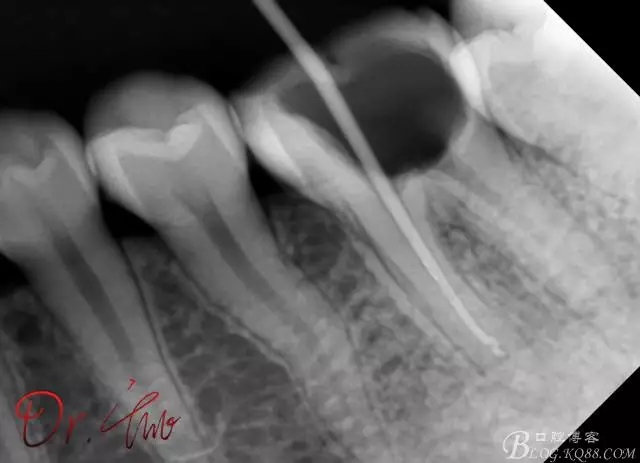

試主尖,近中頰側(cè)試主尖,此時(shí)手用銼02錐度的已擴(kuò)到30號(hào),可以明顯感覺到臺(tái)階位置,挫預(yù)彎后找好正確位置可順利到達(dá)根尖,但是機(jī)用銼就是下不去,也是郁悶

640.webp (9).jpg

試主尖,在30號(hào)02錐度K挫到達(dá)根尖后,用02錐度牙膠尖找準(zhǔn)位置,進(jìn)行試尖

640.webp (10).jpg

最后根充,明顯可看到臺(tái)階位置,期待預(yù)后效果

640.webp (11).jpg